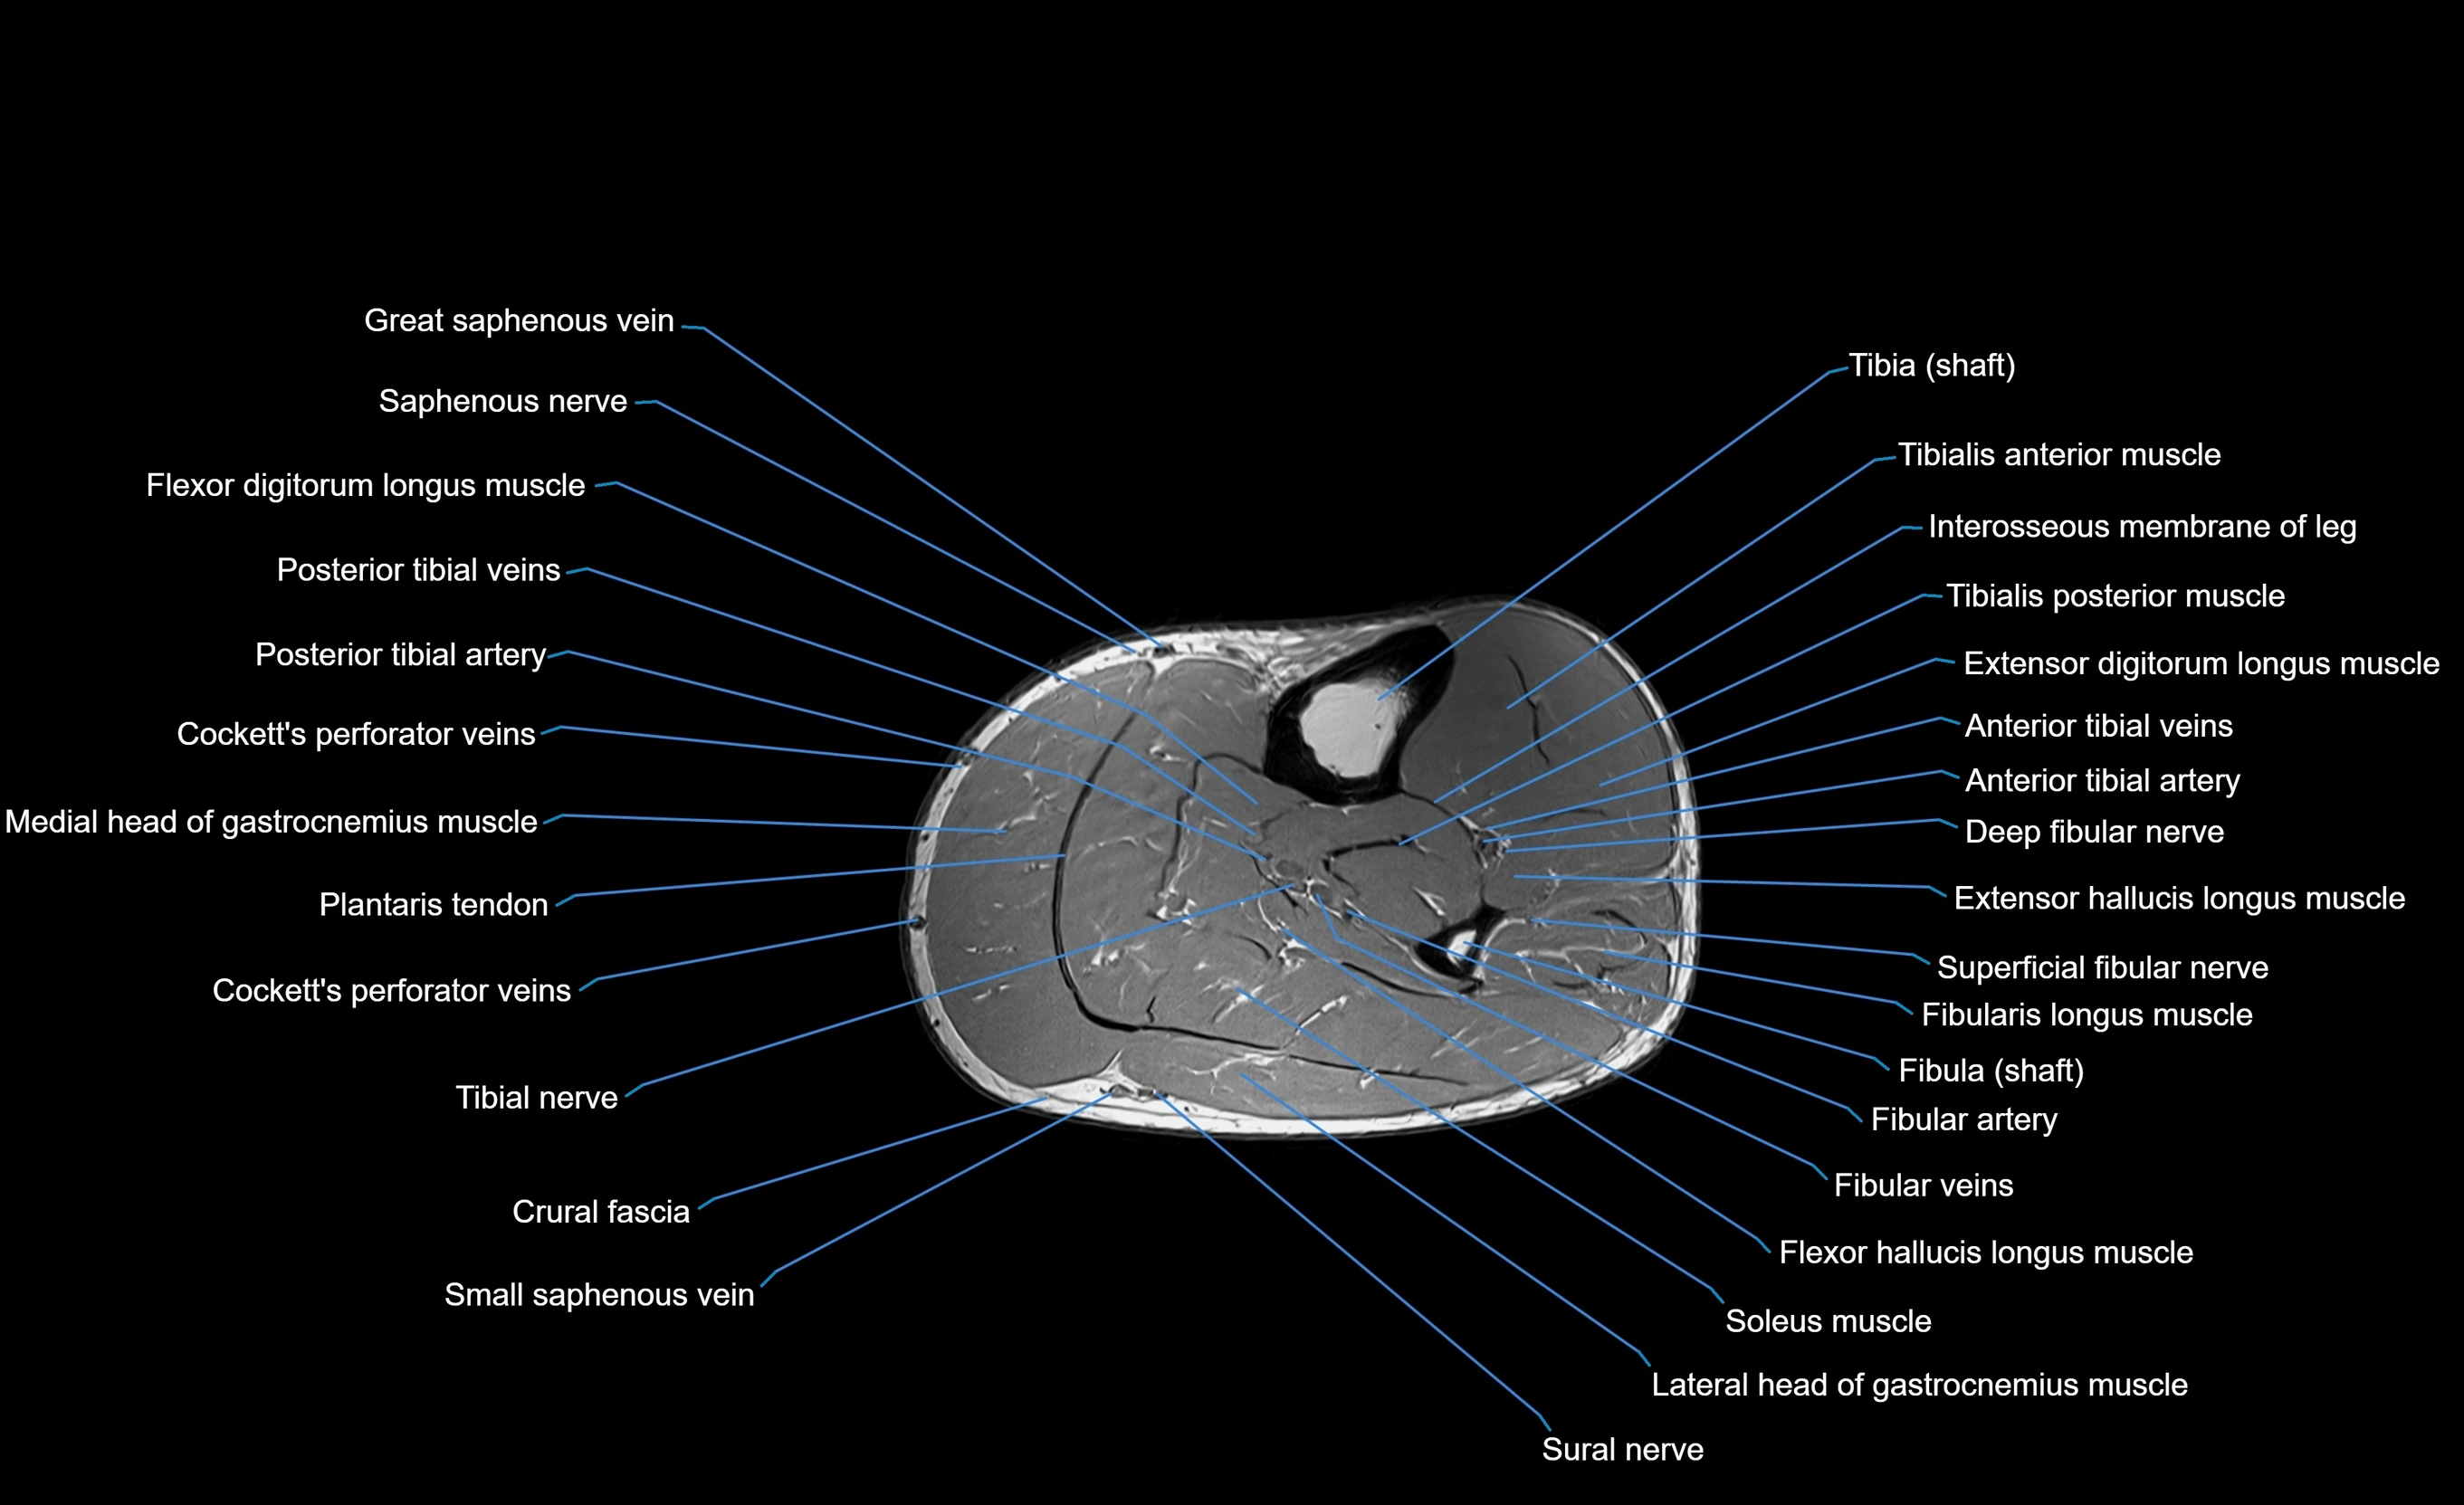

MRI image